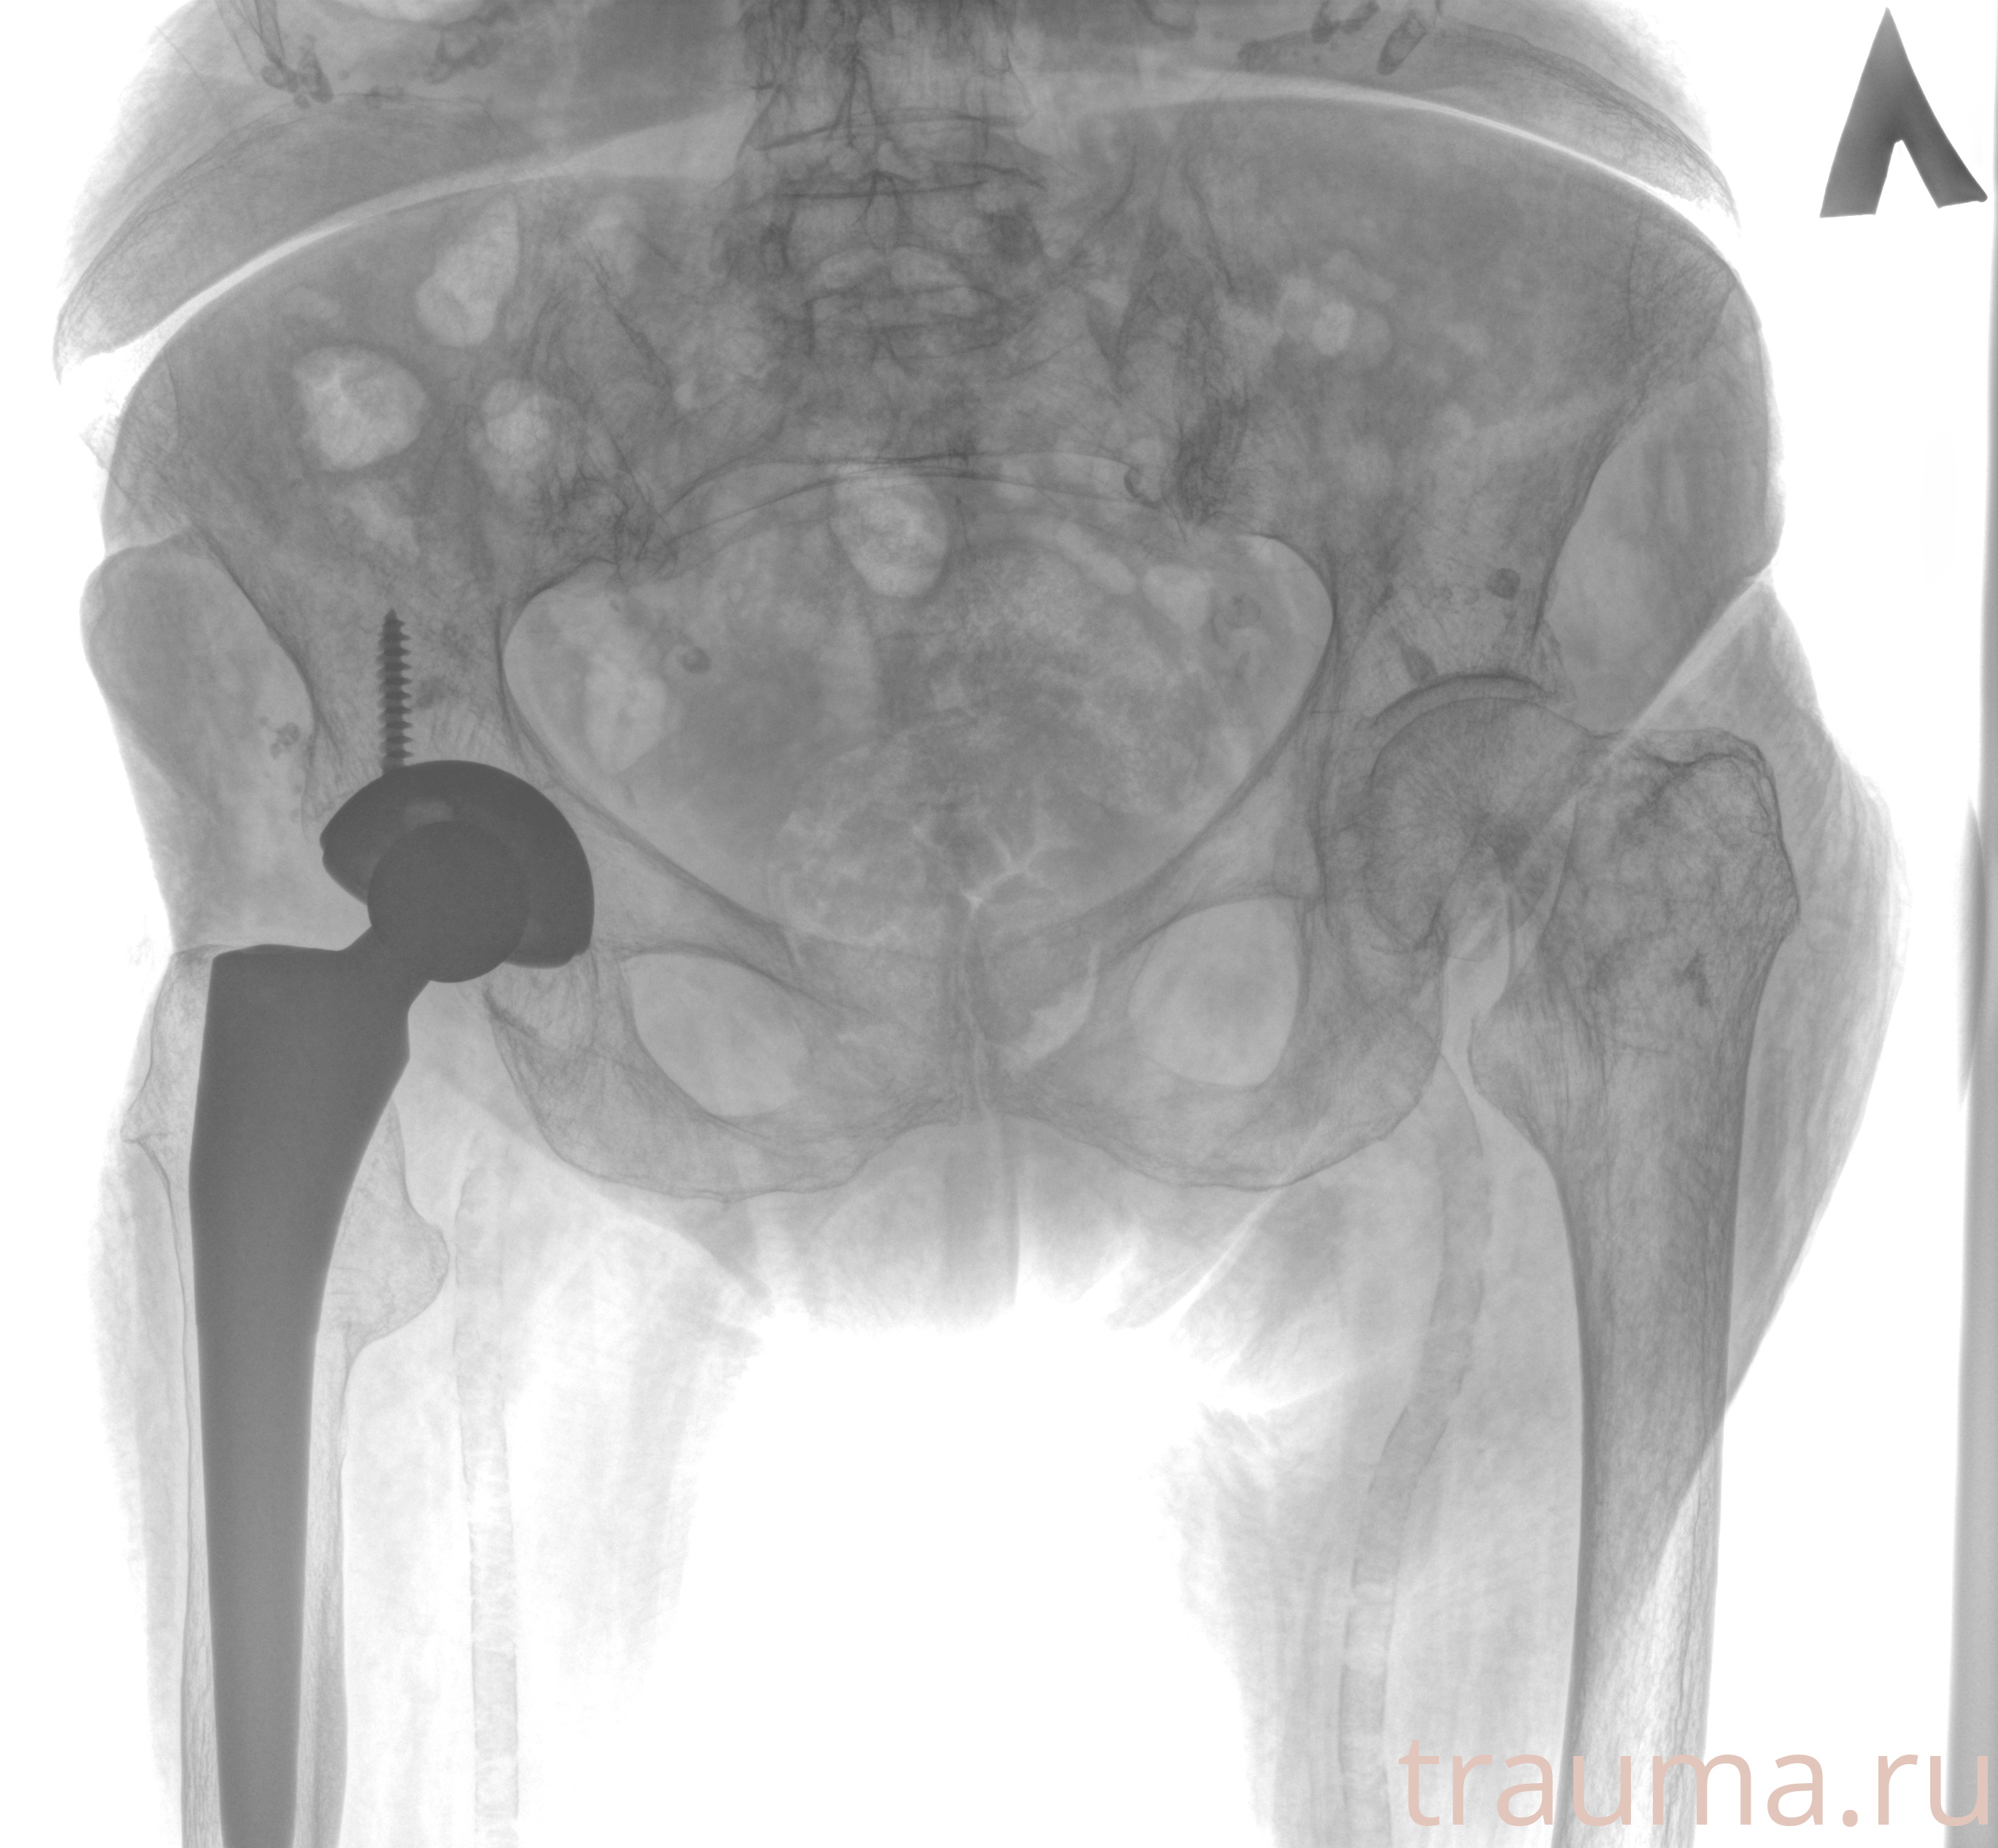

Рентгенограммы

Рентген на дому: по вашему адресу приезжает врач-рентгенолог, травматолог-ортопед с мобильным рентгеновским аппаратом, проводит диагностику травмы или заболевания, делает необходимые рентгенограммы, дает рекомендации по дальнейшему лечению. Получить качественные снимки в домашних условиях возможно благодаря уникальной методике, разработанной МосРентген Центром для института  Склифосовского